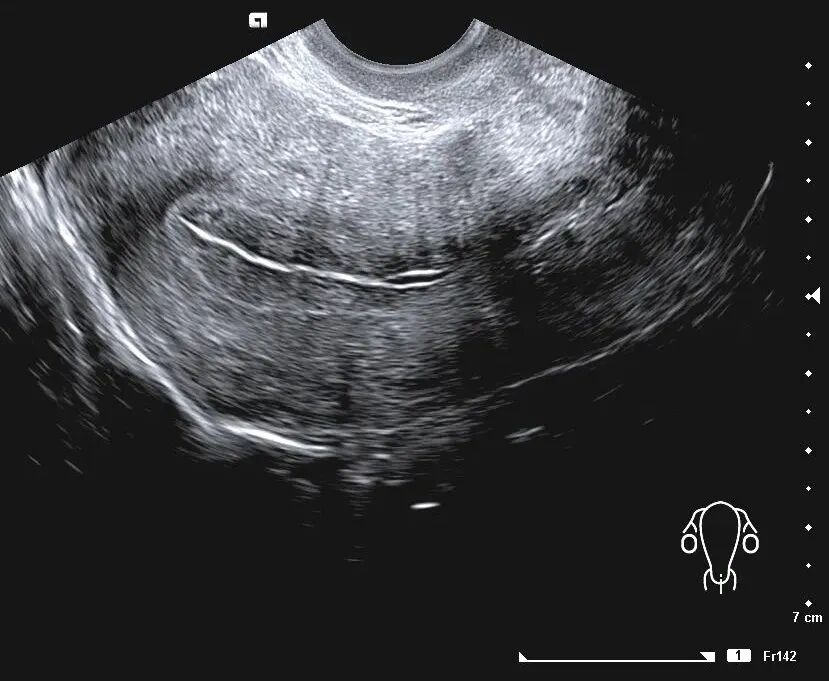

阴道B超是目前临床最常用的评估子宫内膜容受性的无创的方法,可以直接观察到内膜的厚度、类型、容积与血流、蠕动波等。

② 子宫内膜类型

子宫内膜类型分为 A、B、C 3 种。

A型,也就是三线型内膜;

B型,为弱三线型;

C型,均质强回声。

C型,宫腔中线回声模糊

B型,子宫内膜呈现为相对均匀的中等回声内膜,宫腔中线尚清楚

A型,三线呈均质线状的高回声,三线和子宫肌壁及宫内膜的分界比较清楚

取卵日、移植日子宫内膜呈三线征,即A型者,妊娠率显著高于后两者。

目前大多数研究证明, A型子宫内膜临床妊娠率显著高于 B、C型子宫内膜。